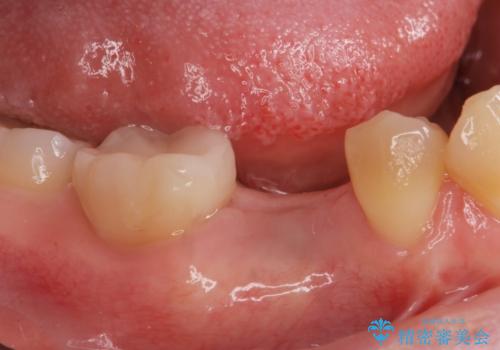

- 過去に抜けてしまった歯のところにインプラントを入れたいとの事で来院。

併用して銀歯も気になるとの事でしたのでセラミック治療も行いました。